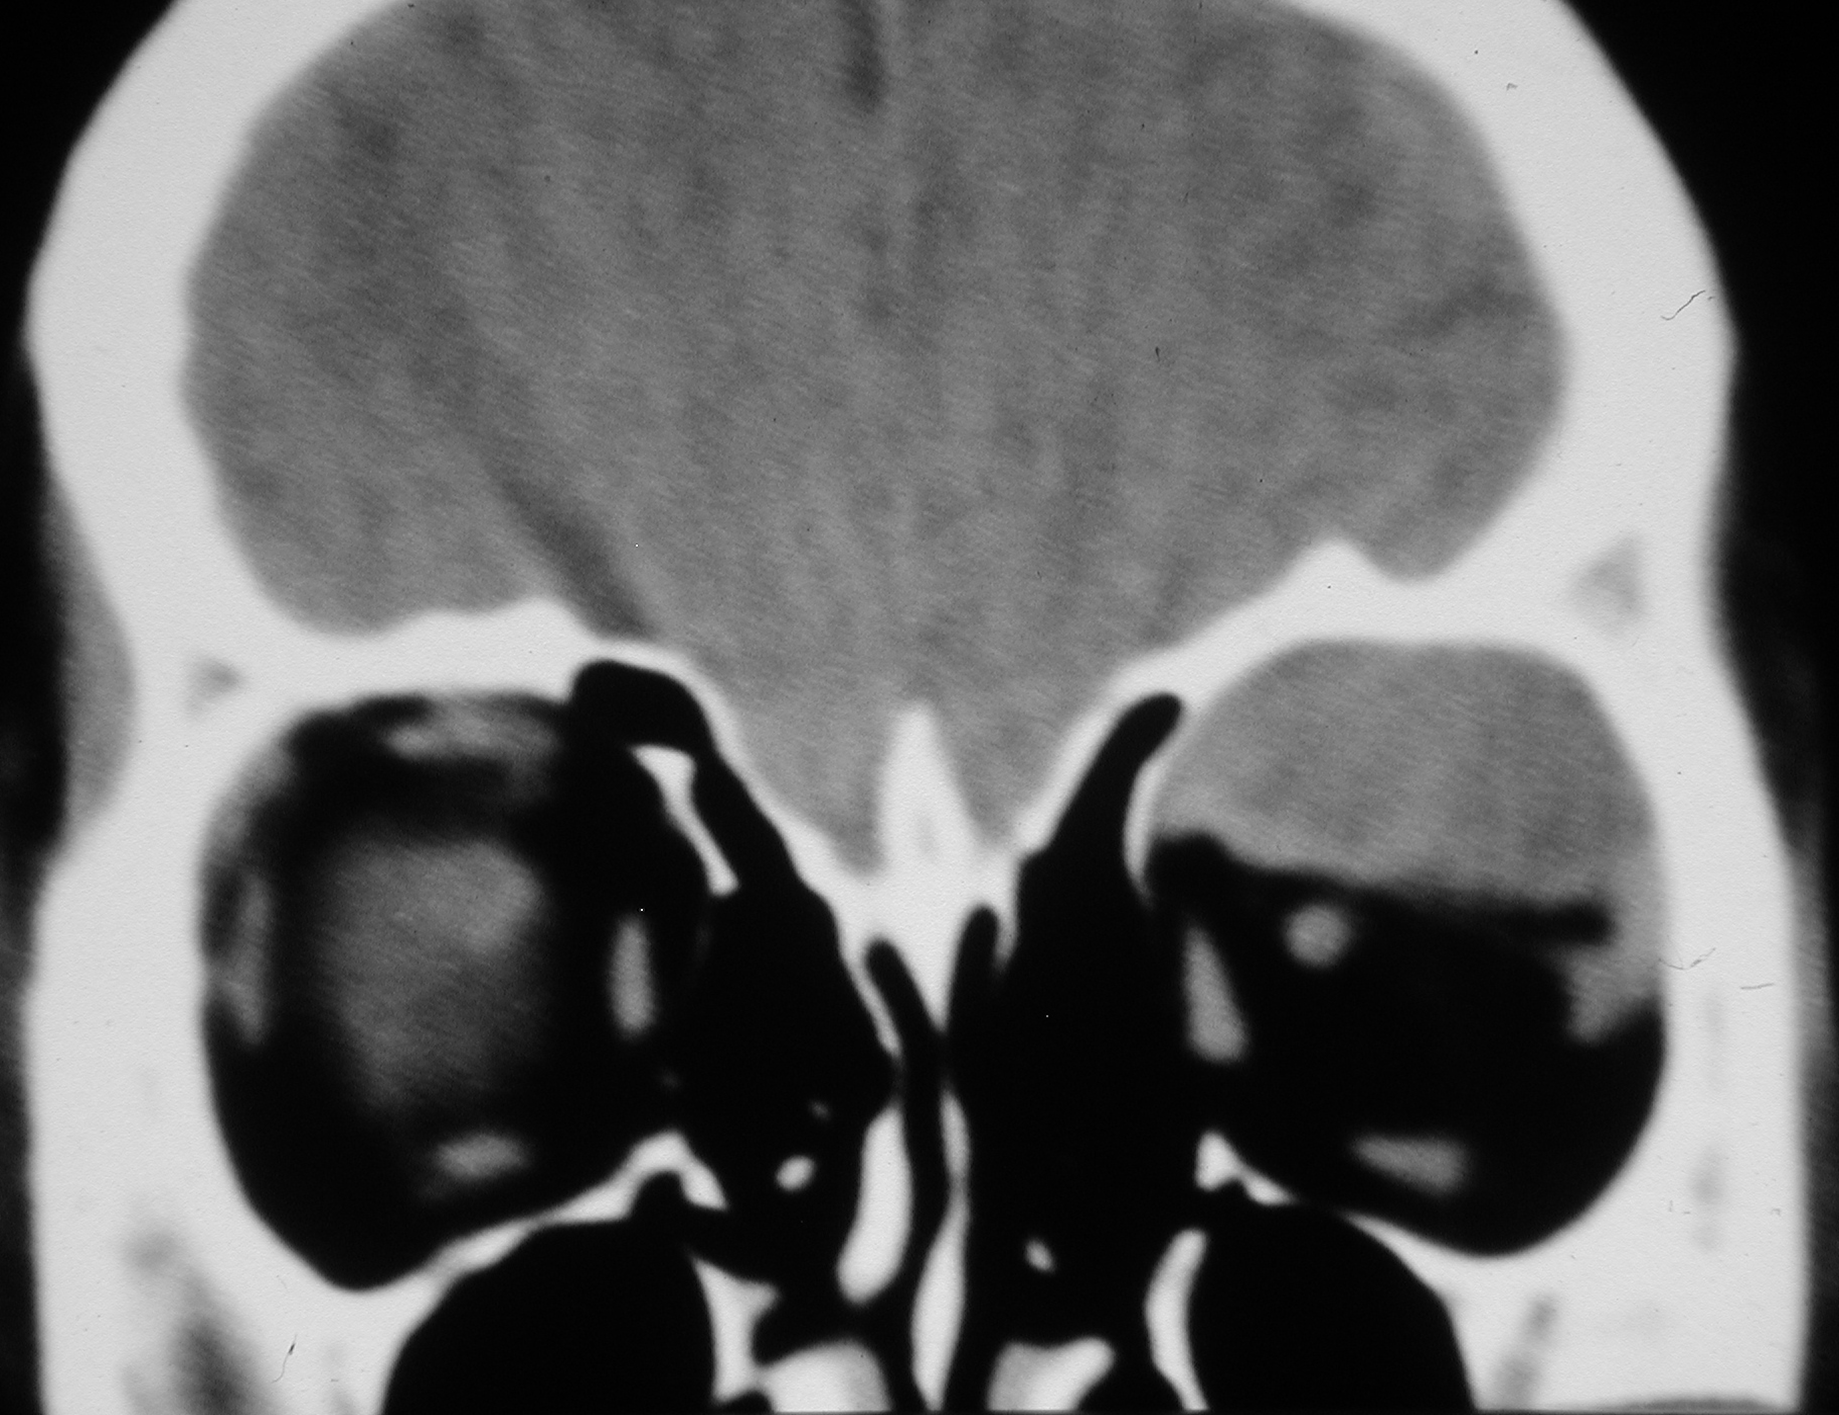

- Figure 5. CT scan of orbits showing subperiosteal haematoma